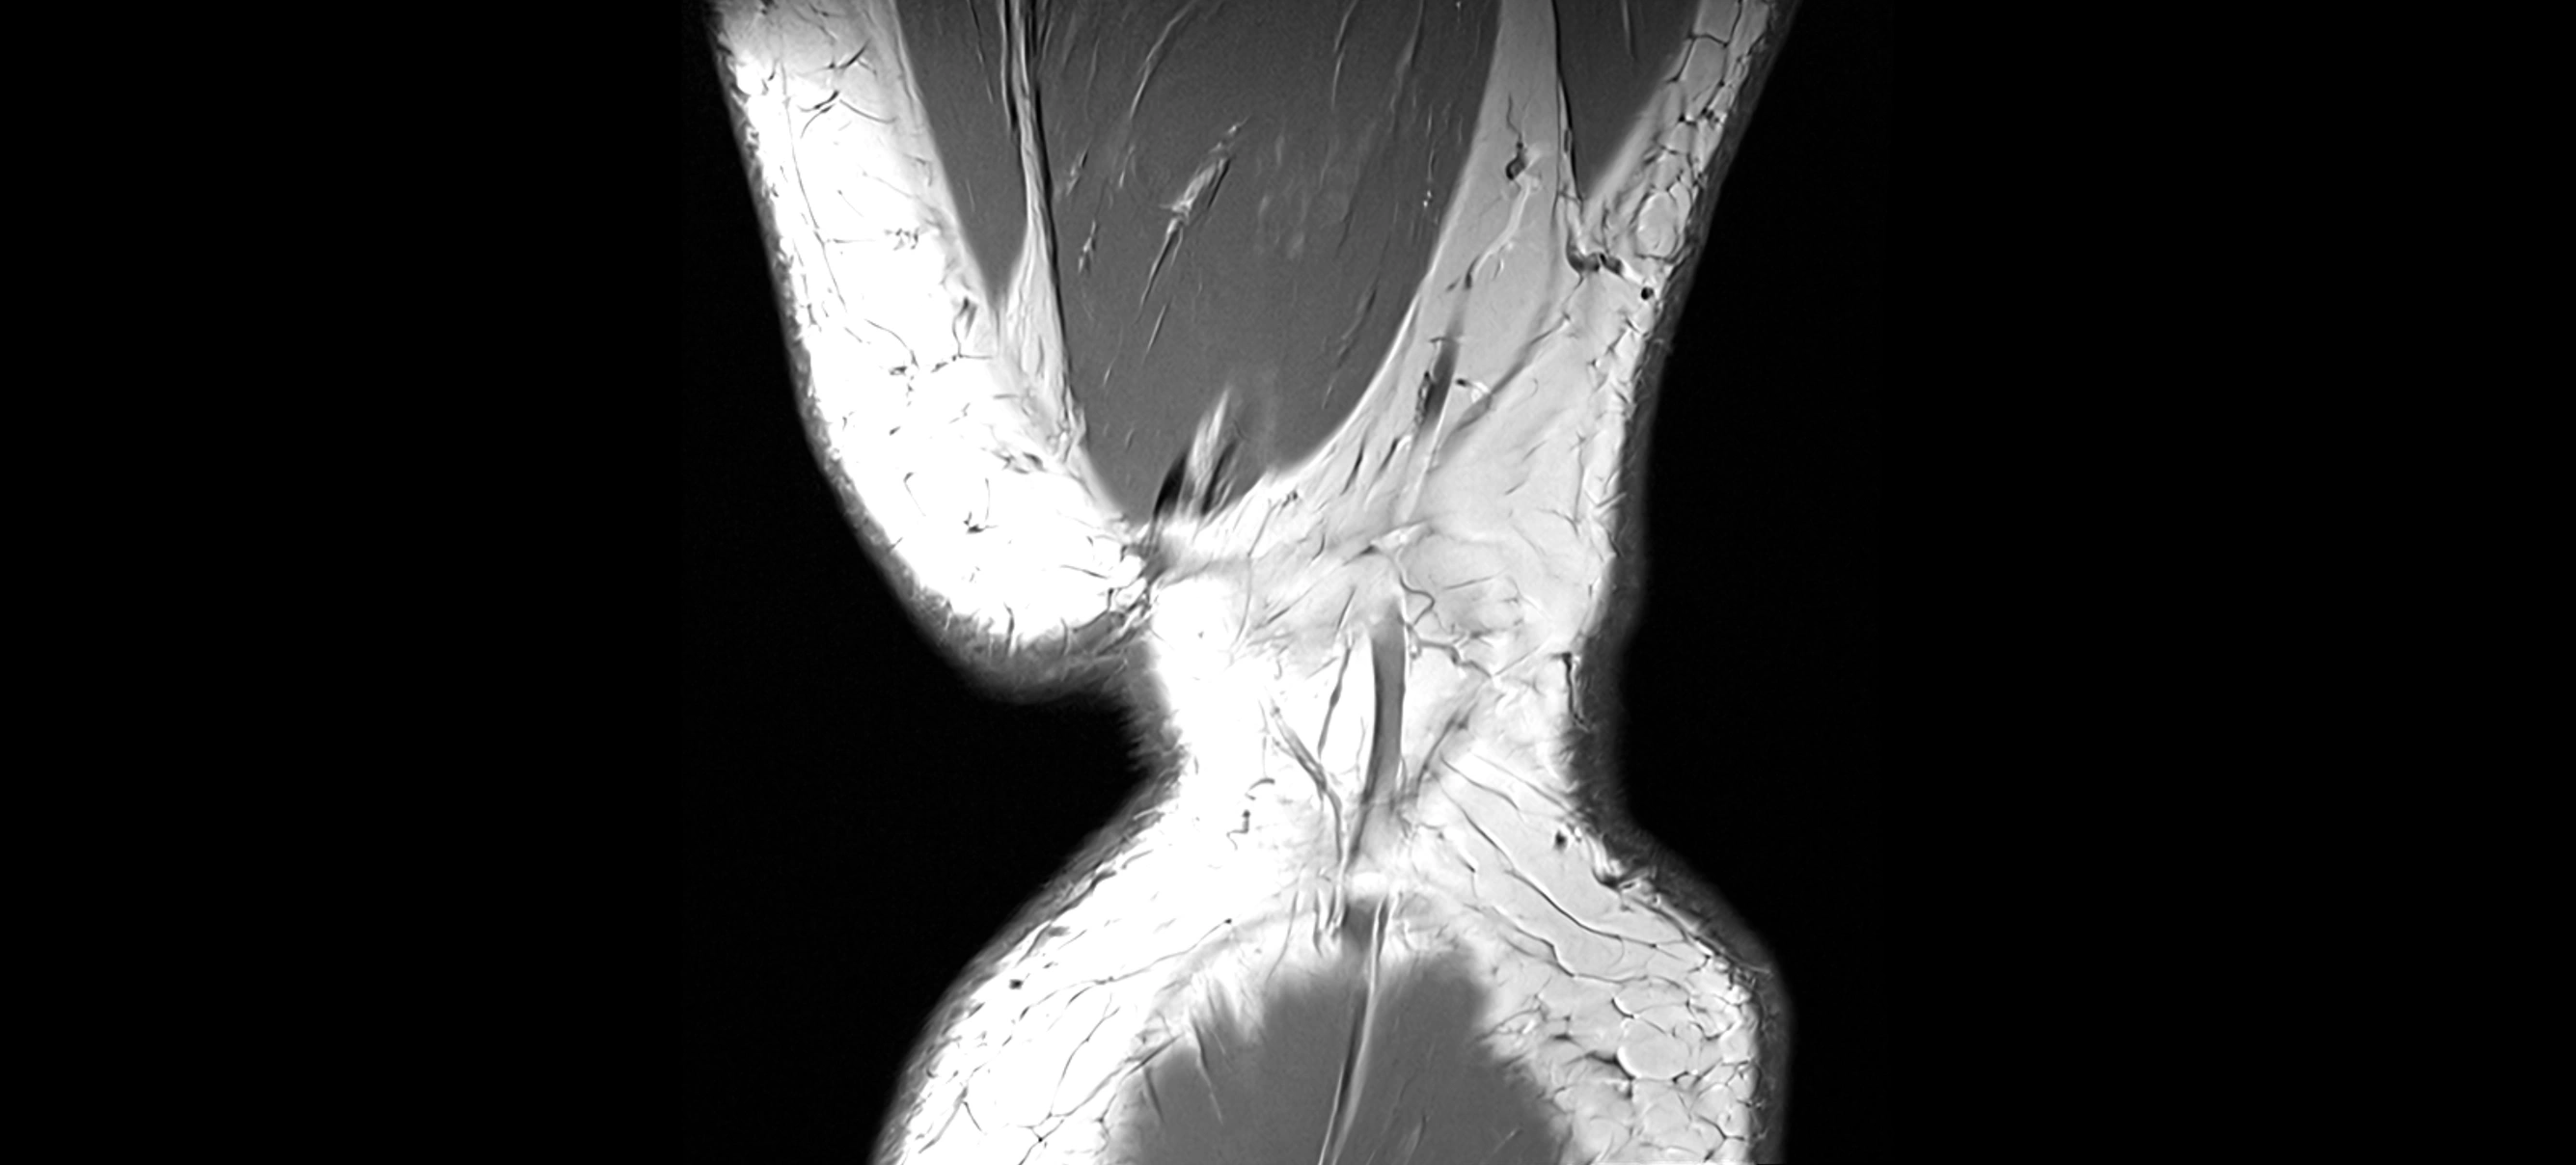

MRI Appearance

T1-weighted images:

• Normal ACL appears as a low-signal band-like structure crossing the intercondylar notch

• Surrounded by intermediate signal synovial fluid and fat planes

T2-weighted images:

• Normal ACL remains low signal

• Partial or complete tears appear as discontinuity, increased signal, or fiber laxity